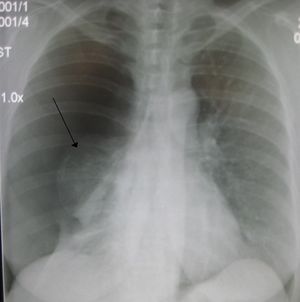

Right sided spontaneous pneumothorax. An arrow indicating the edge of the collapsed lung.